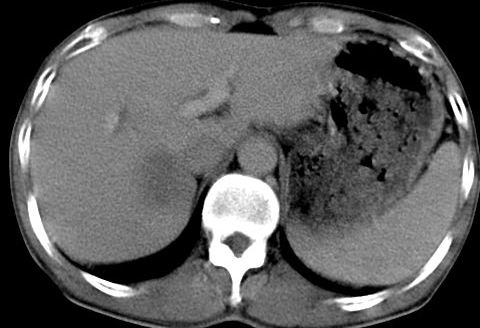

病人资料:男,50岁,上腹部隐痛,消瘦乏力,有乙肝病史二十余年,b超提示肝内内占位。

由于是基层医院,机器速度跟不上,增强效果差,请各位老师也看看!

肝右叶后段低密度灶,增强受机器限制,特点不明显,无等密度充填及周围强化,结合病人乙肝史20年,首先考虑肝癌。

肝右后叶占位,增强时期没抓好,特点不明显,结合病史首先考虑原发性肝癌

肝右叶后下内侧段占位:肝癌可能性大。胰腺占位可能,病人没有空腹准备。

考虑肝右叶后下内侧段占位:肝癌可能性大。增强效果很不理想。